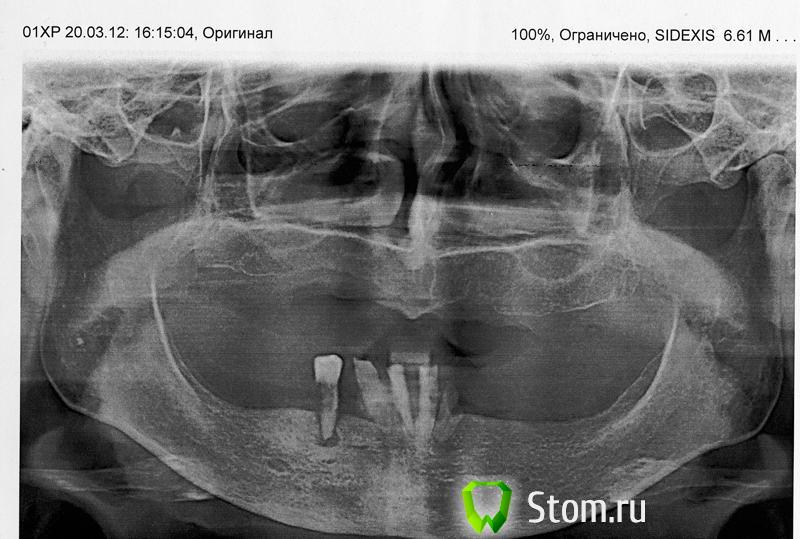

Bankirsha77 Опубликовано 14 апреля, 2012 Поделиться Опубликовано 14 апреля, 2012 (изменено) Добрый день, Прошу дать советы по поводу протезирования женщине 63 лет. Снимок приложен Изменено 14 апреля, 2012 пользователем Bankirsha77 Ссылка на комментарий

o1egator Опубликовано 14 апреля, 2012 Поделиться Опубликовано 14 апреля, 2012 Все удалить. А дальше либо полное съемное протезирование, либо имплантация. 1 Ссылка на комментарий

Dr.Ru Опубликовано 14 апреля, 2012 Поделиться Опубликовано 14 апреля, 2012 Все удалить. А дальше либо полное съемное протезирование, либо имплантация.+1 Ссылка на комментарий

Vitasem Опубликовано 28 апреля, 2012 Поделиться Опубликовано 28 апреля, 2012 наверно , чтобы акцентировать что протезы должны быть бюджетные.Тогда без "либо имплантация" Ссылка на комментарий